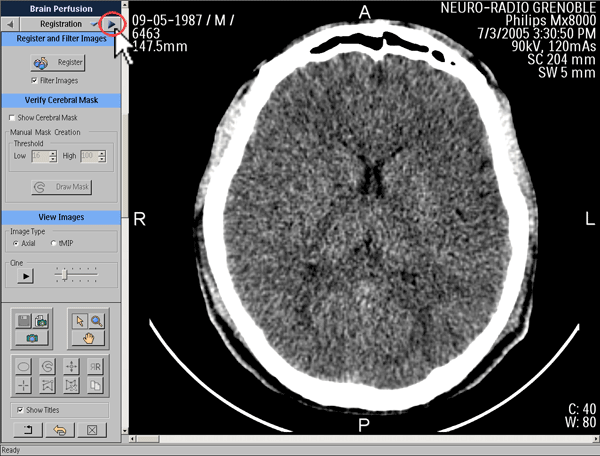

Post-traitement

Recalage des images